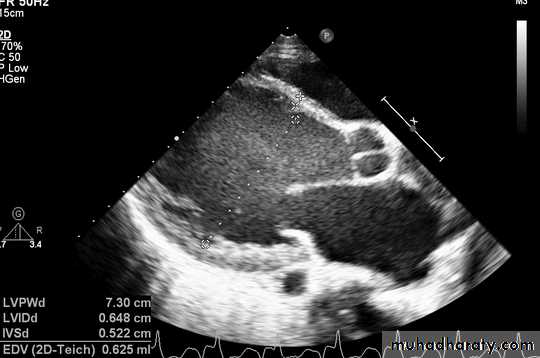

ECHO Echocardiography is diagnostic

The hypertrophy may be generalised or confined largely to the interventricular septum (asymmetric septal hypertrophy or other regions (e.g. apical hypertrophic cardiomyopathy)

Dynamic LV outflow tract obstruction ( atleast >30 mm, usually > 50mm Hg)Diastolic dysfunction